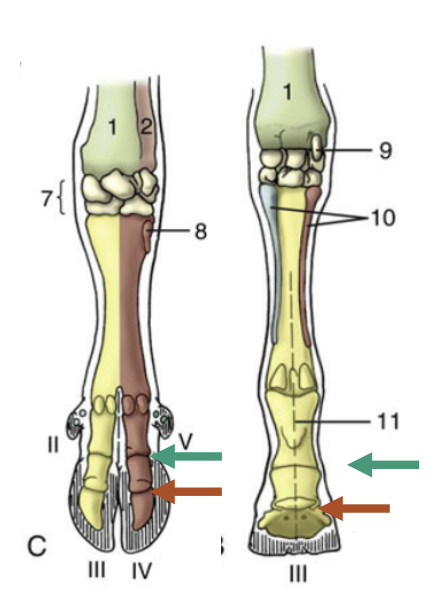

Green arrow?

Proximal interphalangeal joint

Red arrow?

Distal interphalangeal Joint

Which joint it shown?

Metacarpophalangeal Joint